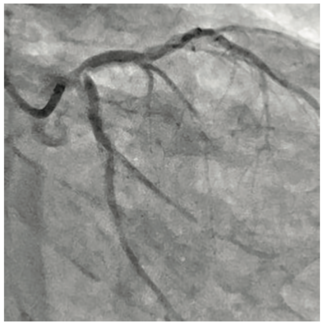

Eric A. Secemsky, MD, MSc, RPVI, FACC, FAHA, FSCAI; Killian J. McCarthy, MB, BCh, BAO

Terumo Interventional Systems has introduced two new players to their interventional arsenal: the Runthrough NS Izanai Coronary Guidewire and Takeru PTCA Balloon Dilatation Catheter. Both devices are designed to improve pushability and...